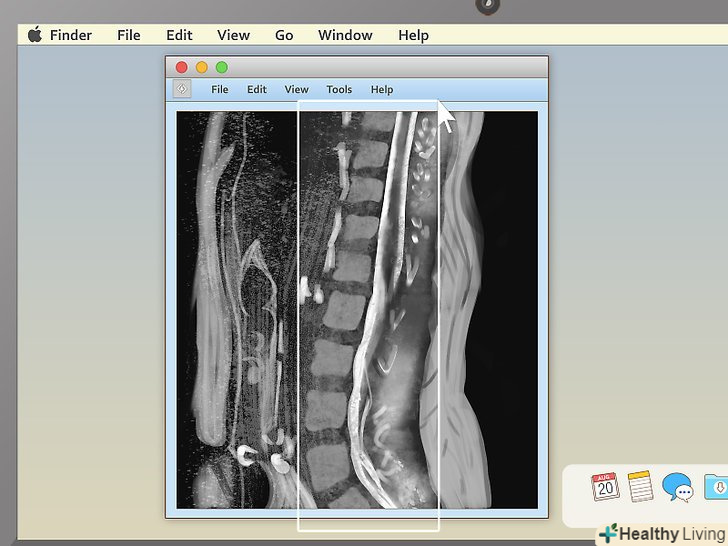

Виберіть відповідний режим перегляду.програми для перегляду МРТ часто вміють показувати більше одного зображення за раз. Завдяки цьому лікарям простіше порівнювати різні проекції однієї і тієї ж області або навіть знімки, зроблені в різний час. Непрофесіоналові краще вибрати режим, при якому буде показуватися тільки одне зображення за раз, і переглядати знімки послідовно. Проте, в програмі повинна бути кнопка, що дозволяє показувати 2, 4 і більше знімків одночасно, тому не бійтеся її натискати.